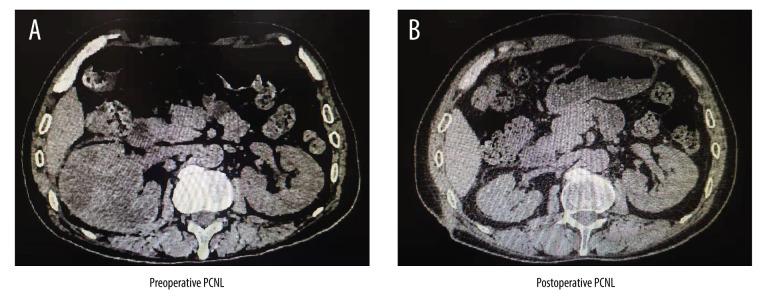

BACKGROUND This study explored the risk factors for renal atrophy after percutaneous nephrolithotomy (PCNL), and provides a reference for clinical prevention of renal atrophy after PCNL. MATERIAL AND METHODS According to the inclusion and exclusion criteria, the clinical data of 816 patients who underwent PCNL in our hospital from May 2013 to February 2018 were retrospectively collected. Depending on whether the patient had kidney atrophy, they were divided into a renal atrophy group and a non-renal atrophy group. We collected and analyzed data on patient sex, age, kidney location, duration of disease, stone size, hydronephrosis, renal calculus position (renal ureteral junction or multiple pyelonephritis-associated stones), operation time, intraoperative blood loss, perfusion pressure, and pyonephrosis. The indicators with statistically significant differences were selected and multivariate logistic regression analysis was carried out to determine the risk factors for renal atrophy. RESULTS Among 816 patients, 49 had renal atrophy and the incidence rate was 6.01%. Univariate analysis and multivariate logistic regression analysis showed that independent risk factors for renal atrophy after PCNL were: duration of the disease longer than 12 months (OR=4.216, P=0.003, 95% CI: 1.714, 7.354), perfusion pressure >30 mmHg (OR=3.895, P=0.001, 95% CI: 1.685, 8.912), moderate and severe hydronephrosis (OR=5.122, P<0.001, 95% CI: 1.847, 9.863), stones located at the junction of the renal pelvis (OR=3.787, P=0.001, 95% CI: 1.462, 7.654), stones located in multiple calyces (OR=4.531, P=0.014, 95% CI: 1.764, 8.196), and pyonephrosis (OR=10.143, P<0.001, 95% CI: 2.214, 16.248). CONCLUSIONS The main risk factors for renal atrophy after PCNL are: course of disease more than 12 months, moderate and severe hydronephrosis, pyonephrosis, multiple calyceal stones, stones at the junction of the renal pelvis, and intraoperative high perfusion pressure.